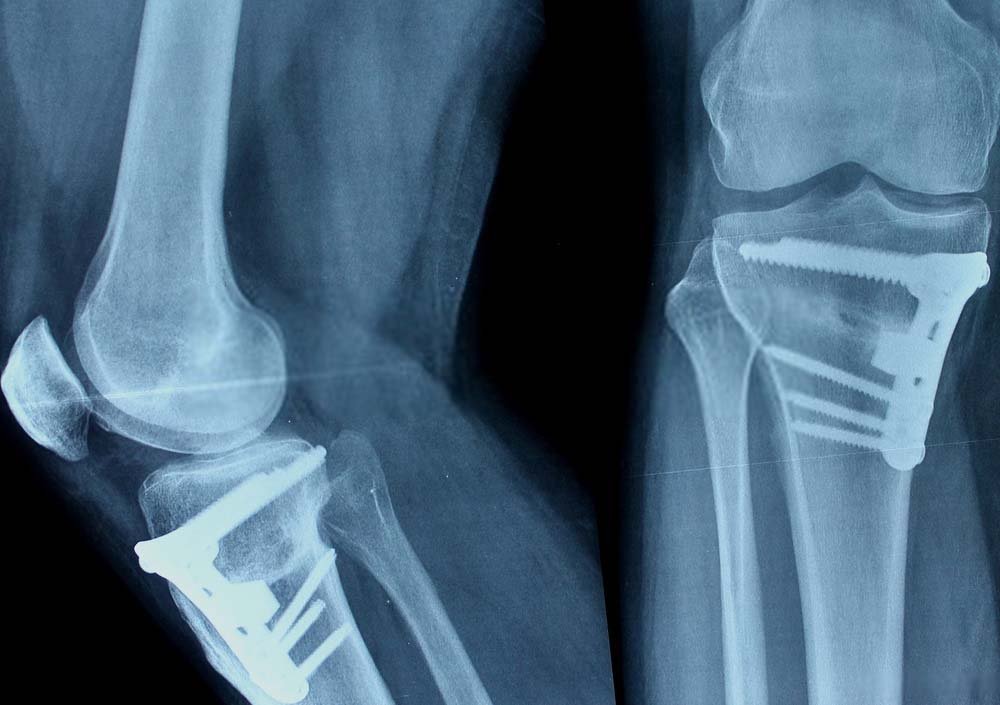

During this procedure, a cut is made on the inside of the tibia, under the unhealthy side of the knee. Using special osteotomes the cut is then opened straightening the leg. This is then fixed with a plate, with or without bone graft.

Osteotomies of the thighbone (femur) are done using the same technique. They are usually done to correct a knock-kneed alignment.

Doctor visit. You will see Dr. Jay for a follow-up visit after surgery. X-rays will be taken so that he can check how well the osteotomy has healed. After the follow-up, Dr. Jay will tell you when it is safe to put weight on your leg, and when you can start rehabilitation.